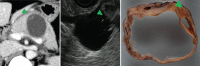

Endoscopic ultrasound (EUS) is a key modality for the evaluation of suspected pancreatic cystic neoplasms (PCNs), as the entire pancreatic gland can be demonstrated with high spatial resolution from the stomach and duodenum. Detailed information can be acquired about the internal contents of the cyst(s) [septum, capsule, mural nodules (MNs)], its relation with the main pancreatic duct (MPD), and any parenchymal changes in the underlying gland. PCNs comprise true cysts and pseudocysts. True cysts can be neoplastic or nonneoplastic. Here, we describe serous cystic neoplasm (SCN), mucinous cystic neoplasm (MCN), and intraductal papillary mucinous neoplasm (IPMN) as prototype neoplastic cysts, along with nonneoplastic lymphoepithelial cysts (LECs).